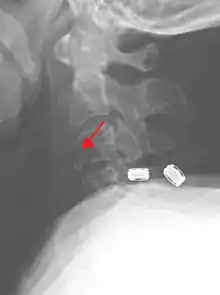

Teardrop fracture of C3 (sagittal CT)

Teardrop fracture of C3 (lateral X ray)